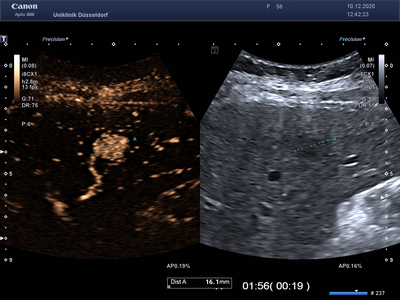

Die Kon­trast­mittelsonographie (KM-Sonographie oder CEUS – contrast enhanced ultrasound) ist ein wichtiges diagnostisches Verfahren, mit dem Tumore der Leber und anderer innerer Organe (z. B. Nieren, Milz, Bauchspeicheldrüse) beurteilt werden können. Neben Tumoren können auch andere Veränderungen dieser Organe charakterisiert werden (z. B. entzündliche Prozesse, Durchblutungsstörungen). Bei erfahrenen Untersuchern hat die KM-Sonographie eine ähnlich hohe Aussagekraft wie eine Computertomographie (CT) oder Magnetresonanztomographie (MRT). Zur Beurteilung von Leberzelltumoren ergänzen sich alle genannten Verfahren (KM-Sonographie, CT und MRT).

Für die KM-Sonographie wird ein Kontrastmittel eingesetzt, welches aus sehr kleinen, von einer Fetthülle umschlossenen, Gasbläschen besteht. Es kommen sehr geringe Mengen (wenige Milliliter) des Kontrastmittels zum Einsatz. Nach der intravenösen Verabreichung verlassen die Gasbläschen den Körper innerhalb weniger Minuten über die Lunge. Die Niere wird dabei nicht belastet, so dass die Untersuchung auch bei Patienten mit fortgeschrittener Nierenerkrankung angewandt werden kann. Unerwünschte Wirkungen (z.B. allergische Reaktionen) treten sehr selten auf und sind unabhängig von bekannten Allergien gegen CT- oder MRT-Kontrastmittel.

Die KM-Sonographie ist nicht nur für die Diagnostik von gutartigen (z.B. Hämangiom, fokale noduläre Hyperplasie - FNH, Adenom) und bösartigen Lebertumoren („Leberkrebs“ oder hepatozelluläres Karzinom - HCC, Gallengangkarzinom oder cholangiozelluläres Karzinom - CCC, Metastasen von Tumoren außerhalb der Leber) und entzündlichen Prozessen (z. B. Abszesse), sondern auch für die Verlaufsbeurteilung dieser Veränderungen hervorragend geeignet.